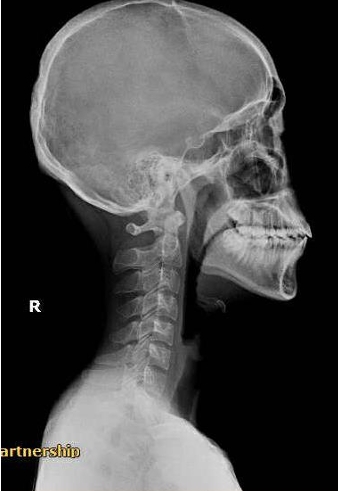

คุณ Elena

อาการ: ปวดคอเรื้อรัง (Neck Pain)

"รักษาด้วย Manual Technique ควบคู่กับการยืดกล้ามเนื้อที่ตึงรั้ง ตอนนี้คอไม่ตึง กลับมาใช้ชีวิตทำงานได้ปกติแล้วครับ"

Before

After